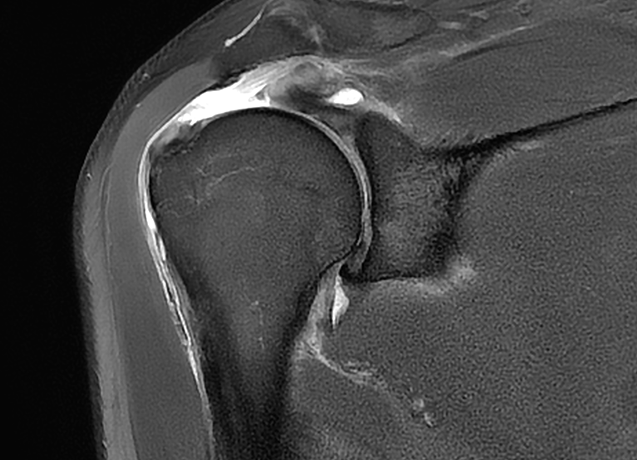

Rotator Cuff Tear

회전근개 파열이란?

회전근개 파열은 ‘회전근개’라고 불리는 어깨관절을 둘러싸고 있는

4개의 힘줄(극상근, 극하근, 소원근, 견갑하근) 중

하나 이상이 파열되는 질환

입니다.

회전근개는 어깨의 안정성을 유지하고, 팔을 들어올리고

회전시키는 동작을 가능하게 하는 중요한 역할을 담당합니다.

어깨 힘줄은 한번 파열되면 자연치유가 어려워

조기 발견과 치료가 중요합니다